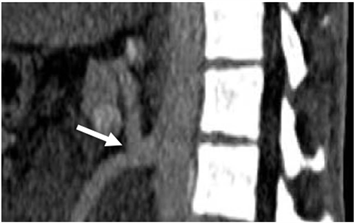

total of 9 patients or 5.6%. Of these, left hepatic artery (Figure 4) and lower right diaphragmatic artery were the most common with three patients each. Then common celiac and mesenteric trunk followed (Figure 5) with 5 patients.

Figure 5. Enhanced abdominal CT-scan showing on 3D reconstruction a common celiac and mesenteric trunk (arrow).